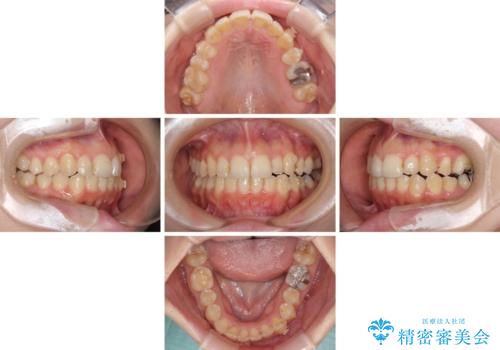

補助装置だけでなく、部分的にワイヤー矯正も使用しましたが、上下のスペースは改善しきれず、側切歯(前から2番目の歯)や顕著な八重歯は、インビザラインで治療するには限界があることがよく分かりました。

より良い仕上がりを希望される場合には、ワイヤー装置による矯正治療がお勧めとなります。